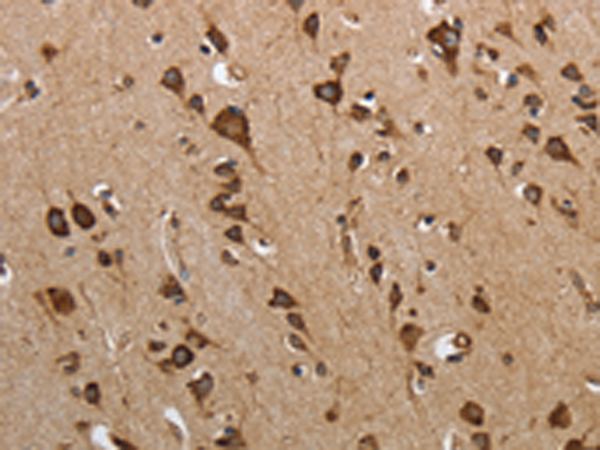

分类: 科研抗体货号: P11108别名: SHO; SHADOO; bA108K14.1应用: IHC反应种属: Human